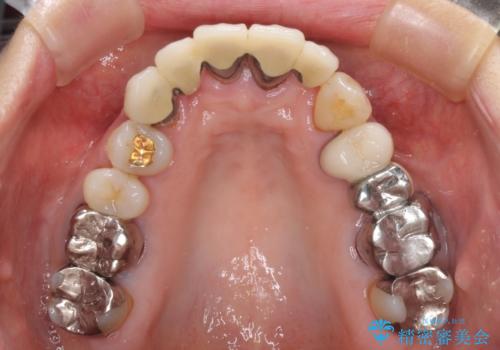

- ブリッジと歯肉の隙間にものが挟まったり空気が抜けたり、歯肉ラインの黒い縁が目立ってしまったりと、前歯のブリッジの作り直しを希望して来院された患者様です。

自然な仕上がりとするため、金属を使用しないオールセラミックブリッジにより補綴治療を行うこととしました。